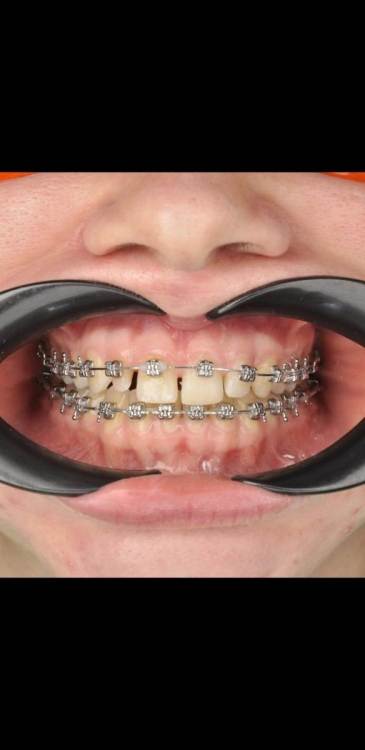

НадеждаВ Опубликовано 3 августа, 2022 Поделиться Опубликовано 3 августа, 2022 (изменено) Добрый день. Имеются 2 шипообразных резца. В стоматологии, где прохожу ортодонтическое лечение убеждают, что просто нарастить только их винирами не выйдет, т.к очень большие расстояния и если закрыть их, то боковые резцы по ширине будут неестественно широкими по отношению к центральным. Уменьшить промежутки тоже не видят возможности, т.к. сейчас передние зубы находятся между двумя нижними, при движении будут друг над другом. Поэтому предлагают установить 6 виниров от клыка до клыка, чтобы закрыть все промежутки и соблюсти соотношение ширины зубов. Действительно ли в моем случае это необходимо и нет реальной возможности ограничиться только двумя реставрациями с сохранением эстетики? Страшно пилить здоровые достаточно эстетичные зубы, особенно центральные резцы. На фото так же макет пластиковый, как мне предлагают сделать. Действительно ли боковые резцы должны быть несколько наклонены к центральным, а не быть абсолютно прямыми и зениты могут быть не четко по центру от зуба, а несколько в сторону уходить? 2. Вопрос касаемо самих виниров. Я хотела бы отбелить свои зубы на сколько получится и чтобы виниры были неотличимы от родных зубов. Я читала, что емах выглядят серовато, подходит ли в моем случае этот способ или лучше виниры, которые делают на рефракторе? Они, как я поняла, выглядят естественнее и тоньше, поэтому и обточки требуют меньше. ( один из Резцов на столько мал, что на него вроде только коронку можно установить). 3. Как оценить опытность врача? У ортопеда опыт всего 4 года, вдруг спилит слишком много. Так же смущает их техник, т.к у него скорее всего тоже небольшой опыт, сможет ли он сделать действительно эстетичную реставрацию? Когда делали макет и меня спрашивали про форму, я сказала, чтобы она максимально была похожа на мою и на макете боковые резцы сделали скошенные, как мои сейчас, но стёсанные, ведь это не эстетично и техник должен был это понимать. Изменено 3 августа, 2022 пользователем НадеждаВ Ссылка на комментарий

chervoncevdaniil Опубликовано 3 августа, 2022 Поделиться Опубликовано 3 августа, 2022 (изменено) Вам делали восковое моделирование и примерку для 6 винировв судя по фото,оплатите и закажите воскове моделироввание с примеркой только на 2 винира и оцените результат. Если вас устроит,то почему делайте,если нет,то обсуждайте другие ваарианты с большим количеством зубов. Исходя из фото номер 2 с моделировкой,все выглядит очень гармонично в случае 6 виниров Изменено 3 августа, 2022 пользователем chervoncevdaniil 1 Ссылка на комментарий

НадеждаВ Опубликовано 4 августа, 2022 Автор Поделиться Опубликовано 4 августа, 2022 @chervoncevdaniil спасибо. Да, макет на 6 зубов. Согласна, что выглядит органично, но я переживаю за зубы, ведь они здоровые, нормальные, а если раз их спилить, то все (это не касается боковых Резцов) я переживаю за целесообразность портить эмаль только ради двух миллиметров винира. По поводу макета на два зуба наверно хорошая идея, только когда мне ставили обратно брекеты, то положение зубов немного поменялось, щель между центральными зубами ушла почти ( хотя изначально у меня вообще ее не было), я правильно понимаю, что по идее, если хоть что-то сдвинулось, то по идее нужно вообще опять гипсовую модель переделывать? ещё сканировали челюсть на 3д, но почему-то этот снимок вообще не использовали. Ссылка на комментарий